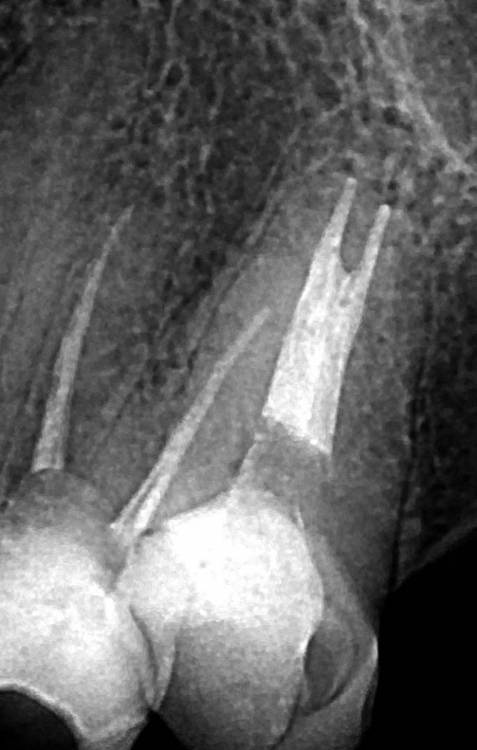

Ico Опубликовано 10 апреля, 2022 Автор Поделиться Опубликовано 10 апреля, 2022 (изменено) 3 отдельных канала в нижнем премоляре,паковка похожая как у Томаса Ланга.Каллибровка,паковка апексов была по S2 протейперу + 25 к. Изменено 10 апреля, 2022 пользователем Ico 1 1 2 Ссылка на комментарий